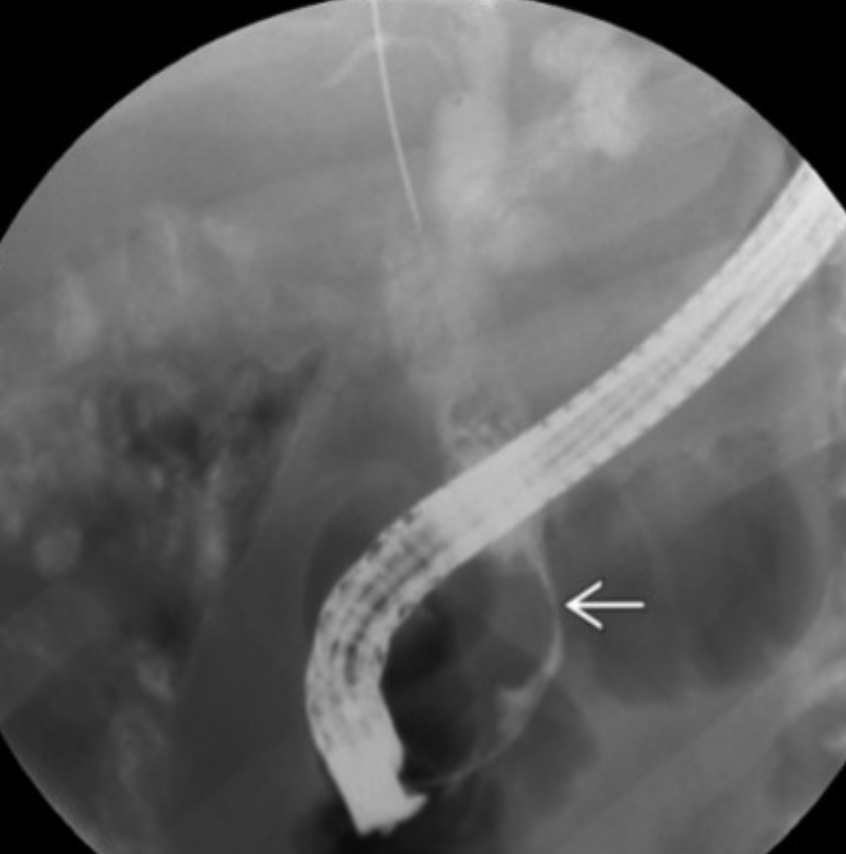

Bile duct infection/inflammation: PSC

ERCP/MRCP: app; which parts of the biliary tree most affected?

How differs from HIV cholangiopathy?

Long-term complications-3